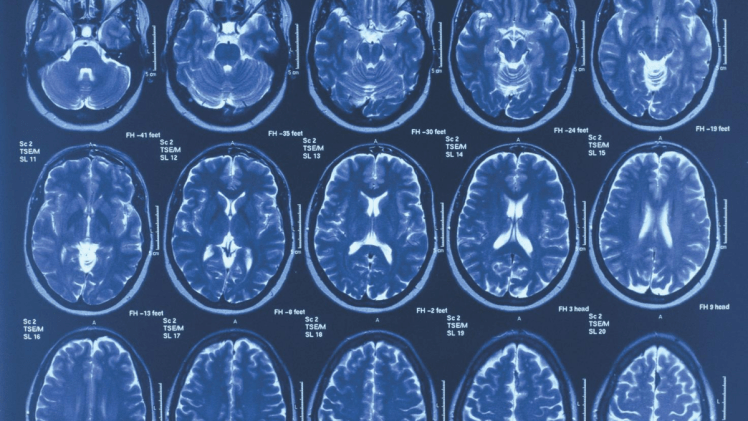

Regional Discussion to Highlight Latest in Alzheimer’s Research

As the largest nonprofit funder of Alzheimer’s research, the Association is committed to accelerating the global progress of new treatments, preventions and, ultimately, a cure. The Alzheimer’s Association funds independent researchers worldwide through our International Research Grant Program. Currently, the Association is investing over $208 million in 590 active best-of-field projects in 31 countries. Our grants […]